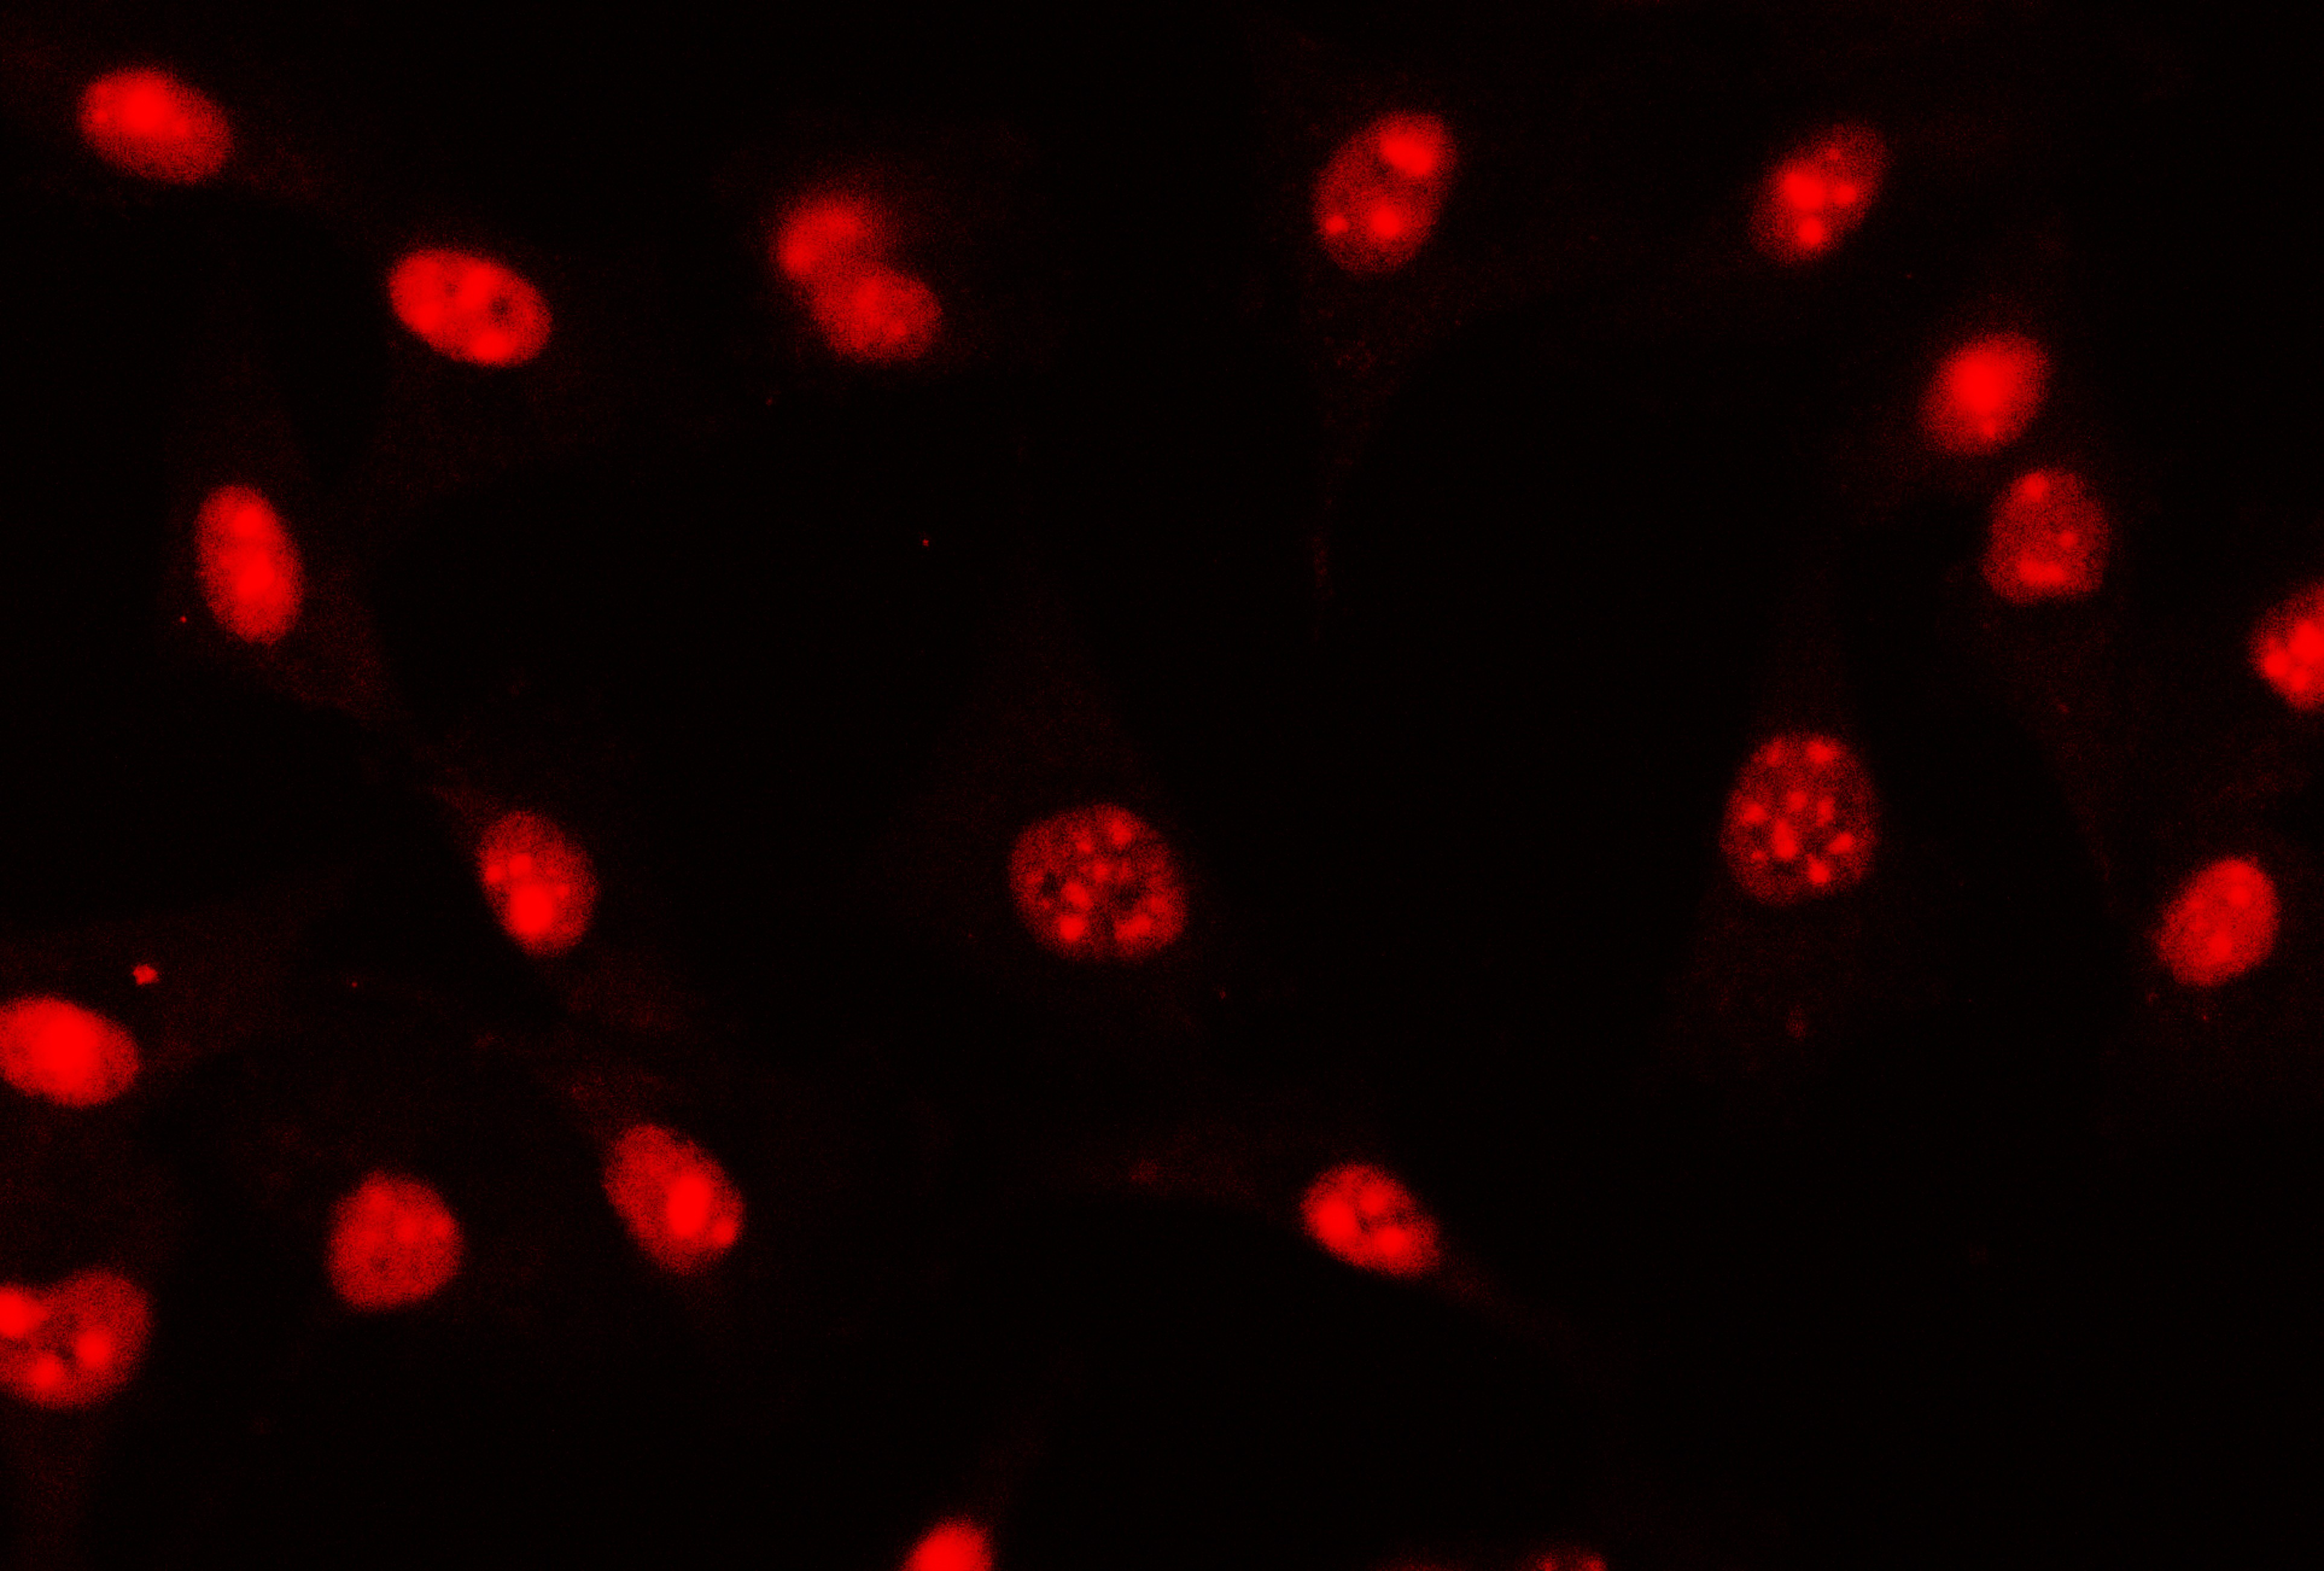

IF analysis of ZEB1 using anti-ZEB1 antibody (M00548-2).

ZEB1 was detected in an immunocytochemical section of U87 cells. The section was incubated with mouse anti-ZEB1 Antibody (M00548-2) at a dilution of 1:100. Dylight550-conjugated Anti-mouse IgG Secondary Antibody (red)(Catalog#BA1134) was used as secondary antibody.